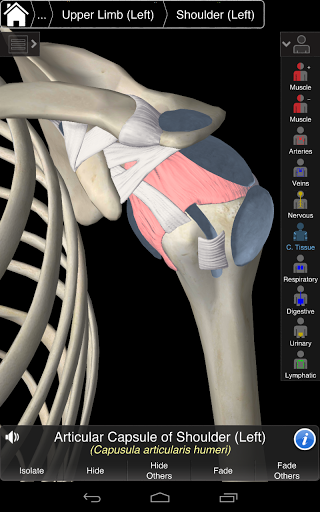

Essential Anatomy 3 représente la toute dernière technologie 3D révolutionnaire et un design innovant. Un moteur graphique 3D de pointe, construit sur mesure par 3D4Medical à partir de zéro, alimente un modèle anatomique très détaillé et fournit des graphiques de qualité exceptionnelle qu'aucun autre concurrent ne peut atteindre.

L'application représente une approche unique à l'apprentissage de l'anatomie générale. Les graphismes sont inégalés et rendent l'apprentissage, grâce à l'utilisation de contenu informatif et de fonctionnalités innovantes, une expérience riche et engageante.

Essential Anatomy 3 est réactif, visuellement magnifique et sans effort. L'application est entièrement 3D, ce qui signifie que vous pouvez voir n'importe quelle structure anatomique dans l'isolement, ainsi que de n'importe quel angle.

CONCEPTION D'INTERFACE PREMIUM

Essential Anatomy 3 est conçu en pensant à l'utilisateur - le corps lui-même devient l'interface. Contrairement à d'autres applications 3D, qui reposent sur des arrangements anatomiques prédéfinis et des dissections régionales pour guider l'utilisateur, l'Anatomie 3 essentielle de 3D4Medical vous permet de trouver ce que vous recherchez sans complication.

---- Plus de 4000 structures anatomiques très détaillées